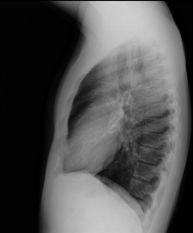

- RX Tórax

Técnica mediante la cual, utilizando rayos X, se obtienen imágenes de la caja torácica (corazón, pulmones, arcos costales, clavículas, etc.) para su estudio. - RX Esternón